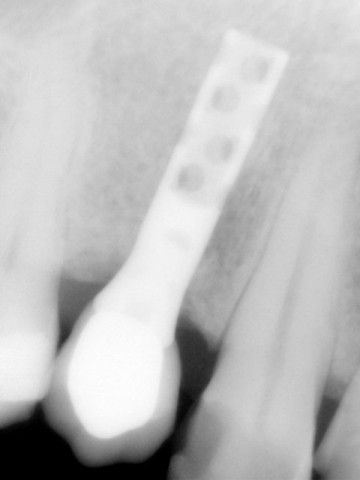

«Το πρώτο μας εμφύτευμα στην Κρήτη»

“Στις παρακάτω φωτογραφίες προβάλλονται δύο παλιά περιστατικά. Το πρώτο είναι το πρώτο μας εμφύτευμα και είναι το μακροβιότερο από όσα έχουν τοποθετηθεί στην Κρήτη! Το δεύτερο είναι μια μεγαλύτερη αποκατάσταση από το 1997”

ΠΡΩΤΟ ΠΕΡΙΣΤΑΤΙΚΟ